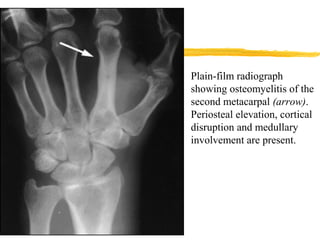

Plain-film radiograph

showing osteomyelitis of the

second metacarpal (arrow).

Periosteal elevation, cortical

disruption and medullary

involvement are present.

Plain-film radiograph showing osteomyelitisof the second metacarpal (arrow). Periosteal elevation, cortical disruption and medullary involvement are present.